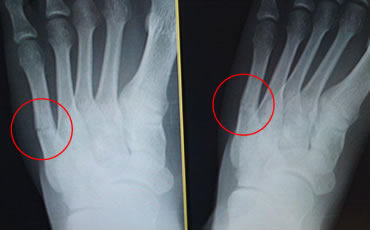

14歳(中学生/バスケットボール選手)男性 症状:中足骨骨折 (酸素カプセル)

回復の経過

酸素カプセル利用経過 2月26日 スタート時

酸素カプセル利用経過 3月19日 初期

酸素カプセル利用経過 4月9日 中期

酸素カプセル利用 4月23日 終了